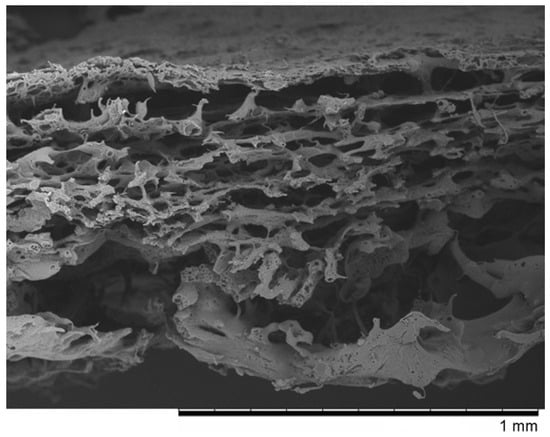

- Wasyłeczko, M.; Sikorska, W.; Przytulska, M.; Dulnik, J.; Chwojnowski, A. Polyester membranes as 3D scaffolds for cell culture. Desalination Water Treat. 2021, 214, 181–193. [Google Scholar] [CrossRef]

- Chwojnowski, A.; Kruk, A.; Wojciechowski, C. The dependence of the membrane structure on the non-woven forming the macropores in the 3D scaffolds preparation. Desalination Water Treat. 2017, 64, 11394. [Google Scholar] [CrossRef]